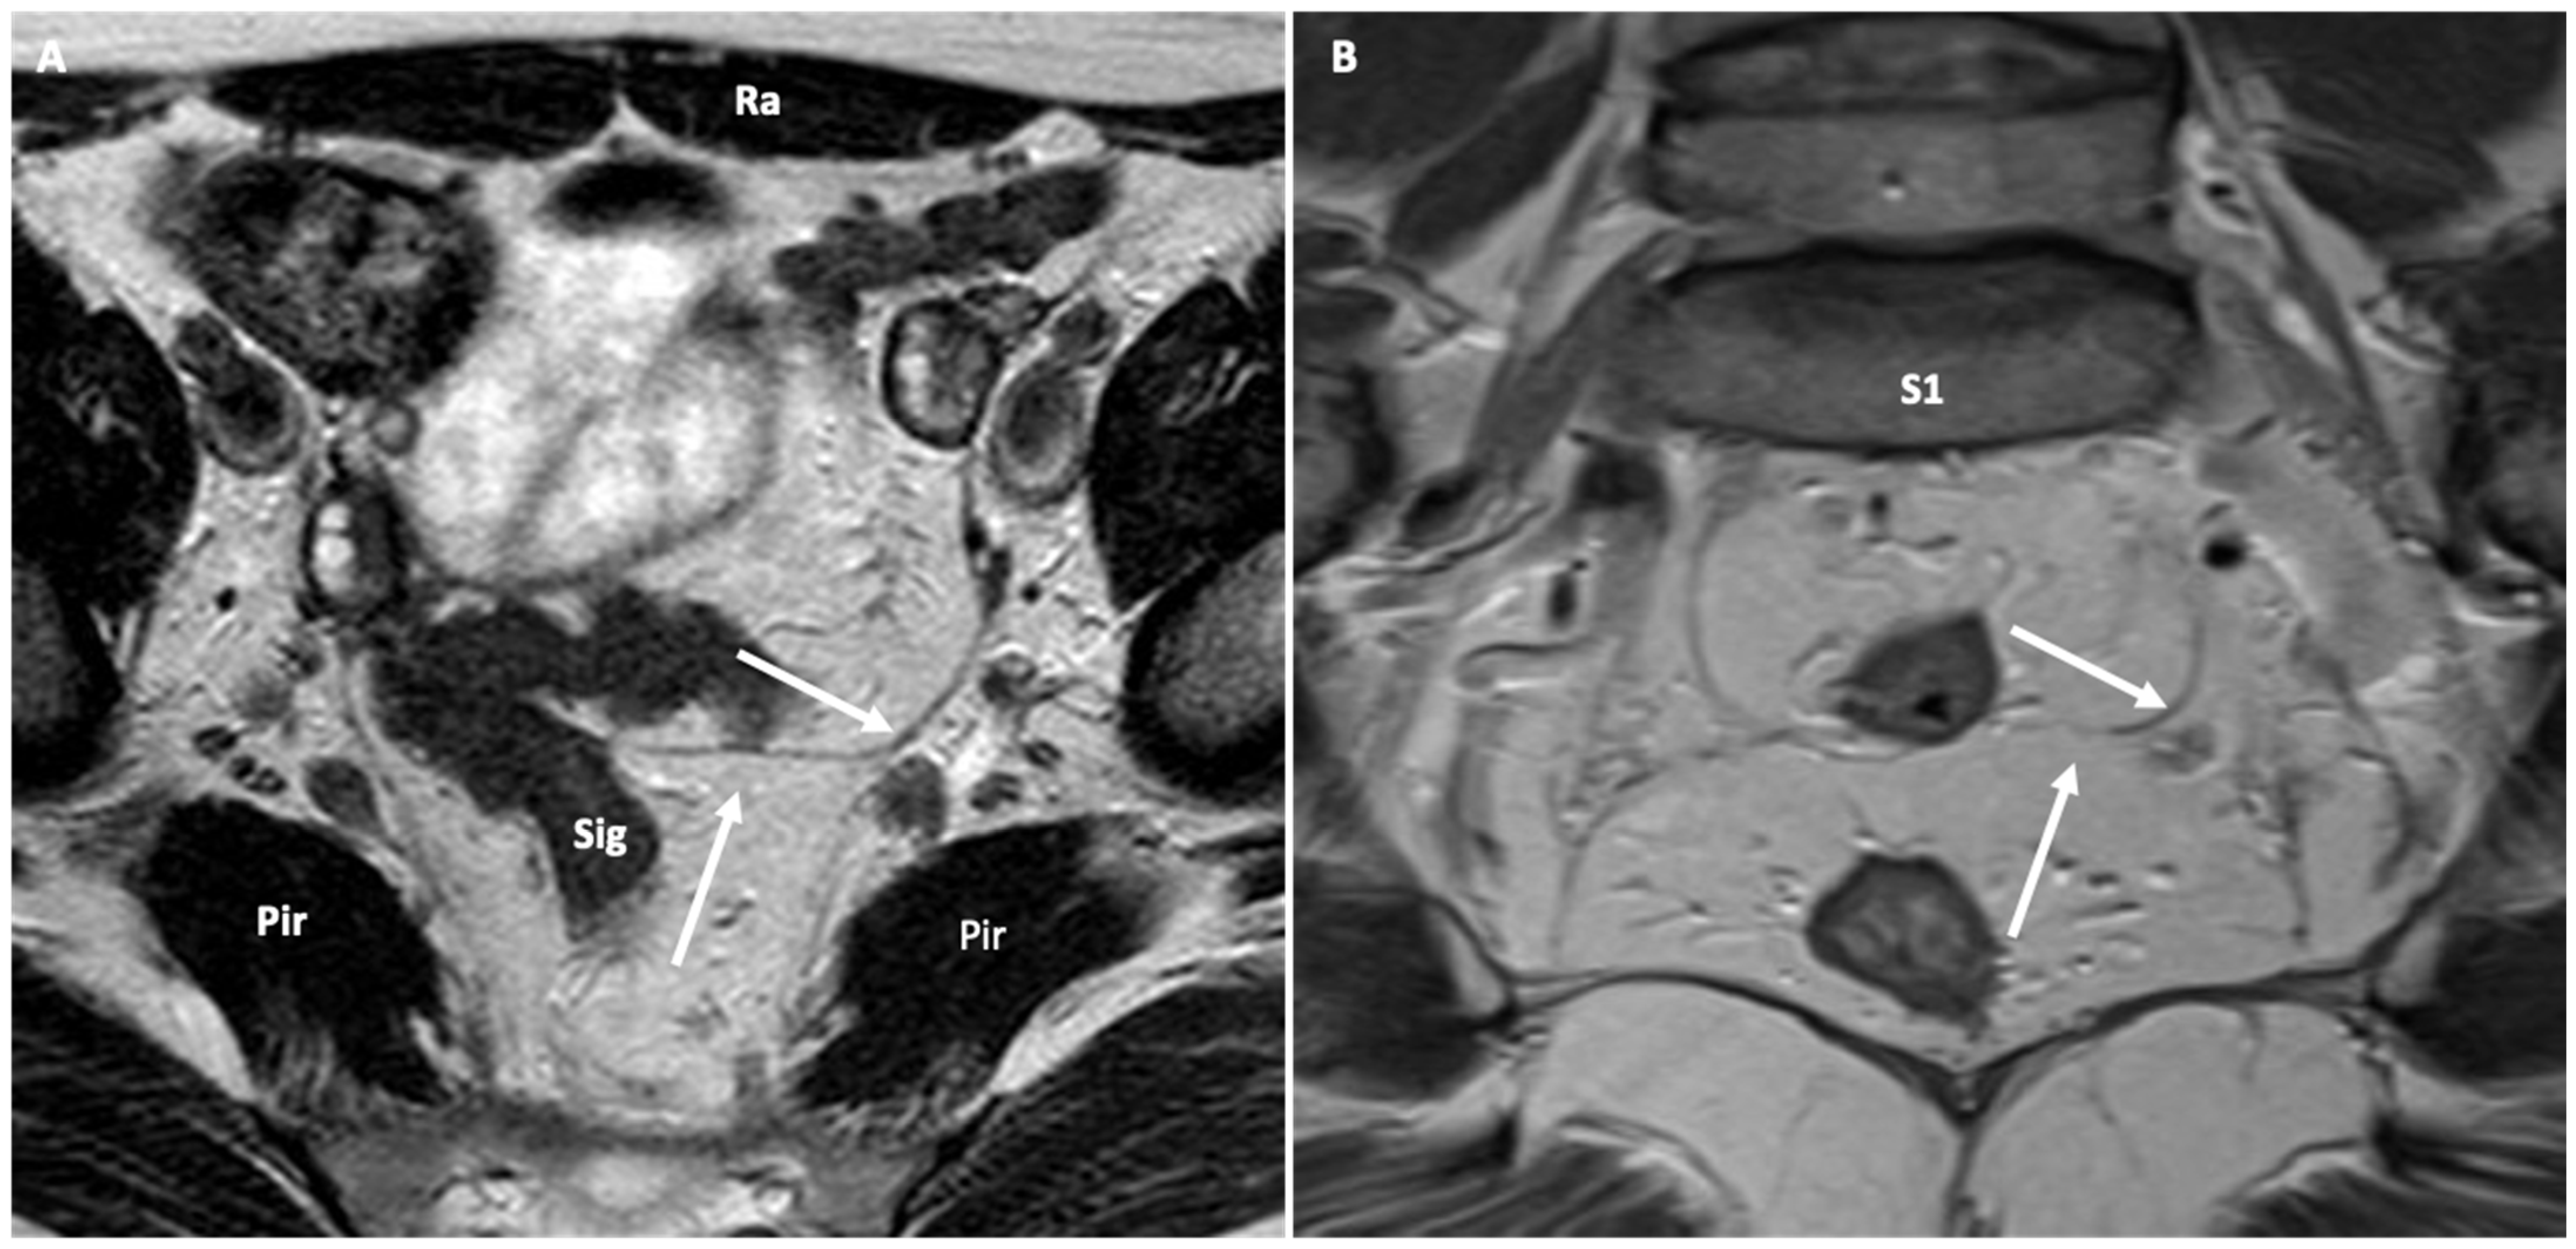

4.1.6. Axial Imaging of the Levator Hiatus

5.2.6. The HMO Classification System

- Pelvic organ descent: defined as the difference between the resting and straining positions of the bladder neck, prostate base, vaginal vault, and anorectal junction (ARJ). This descent is measured relative to a reference line (PCL or horizontal line) and indicated by a number preceded by a minus sign (−) for above or a plus sign (+) for below the reference. Normal values are −3 cm for the bladder base, prostate, and vaginal vault and −2 cm for the ARJ.